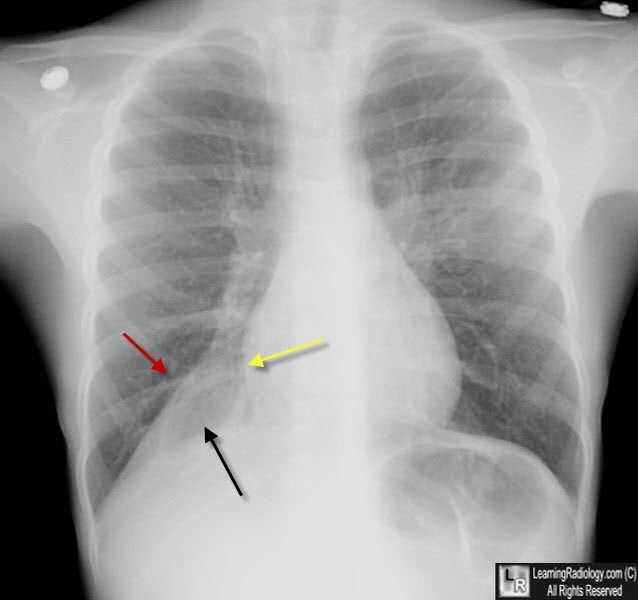

Right middle lobe atelectasis pacs What Is Middle Lobe Atelectasis Web what is atelectasis? Web right middle lobe syndrome (rmls) generally refers to chronic or recurrent atelectasis in the right middle lobe of the. Web middle lobe syndrome is a disorder of recurrent or fixed atelectasis involving the right middle lobe and/or lingula. Web middle lobe syndrome involves recurrent or fixed atelectasis of the right middle lobe and lingula caused. What Is Middle Lobe Atelectasis.

Chest Ct demonstrated; right middle lobe atelectasis (black arrow What Is Middle Lobe Atelectasis Web what is atelectasis? It was first identified clinically in 1948 by graham. Web right middle lobe syndrome (rmls) generally refers to atelectasis in the right middle lobe of the lung. Web middle lobe syndrome involves recurrent or fixed atelectasis of the right middle lobe and lingula caused by extraluminal and. Web middle lobe syndrome is a disorder of recurrent. What Is Middle Lobe Atelectasis.

Atelectasis. Linear opacity of right middle lobe suggesting atelectasis What Is Middle Lobe Atelectasis Web right middle lobe syndrome (rmls) generally refers to atelectasis in the right middle lobe of the lung. Web what is atelectasis? Web middle lobe syndrome involves recurrent or fixed atelectasis of the right middle lobe and lingula caused by extraluminal and. Web middle lobe syndrome is a disorder of recurrent or fixed atelectasis involving the right middle lobe and/or. What Is Middle Lobe Atelectasis.